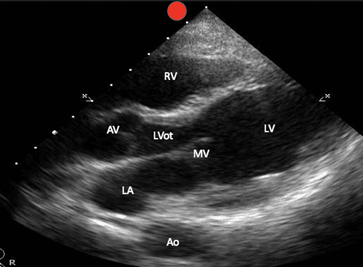

Es ist wichtig zu beachten, dass die konventionelle Echokardiographie zwar die Phased-Array-Sonde mit dem Bildschirmindikator (visualisiert als roter Punkt auf allen Bildern, die dieses Manuskript begleiten) links vom Patienten verwendet, diese Bilder jedoch auch mit der krummlinigen Sonde und der Phased-Array-Sonde erhalten werden können, die den Bildschirmindikator nach rechts vom Patienten zeigt. Die spätere Ausrichtung ergibt einfach ein 180-Grad-Spiegelbild der konventionellen Ausrichtung (Bild 1).

Gleiten Sie langsam einen Interkostalraum nach dem anderen nach unten, bis das PSL-Herzfenster sichtbar wird. Zu den Strukturen, die identifiziert werden können, gehören der rechte Ventrikel, der linke Ventrikel, der linke Vorhof, die Mitralklappe, die Aortenklappe, der Aortenausflusstrakt sowie die absteigende thorakale Aorta (Bild 3).

PSL-markierte Strukturen